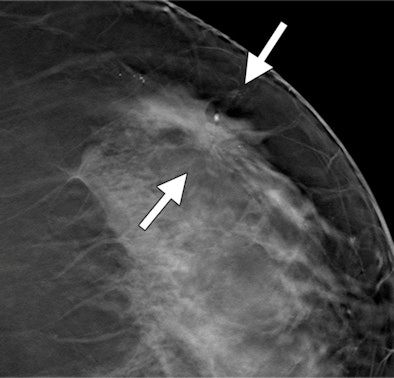

| Images show possible mass in a 54-year-old woman. Craniocaudal spot compression (above) and tomosynthesis (below) show biopsy-proved invasive ductal carcinoma (arrows). The spiculated mass margins are better shown with DBT than in the spot compression image. All images courtesy of RSNA. |